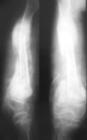

根据病史和临床表现,诊断不难。特别是有窦道及经窦道排出过死骨时,诊断更易。摄X线片可以证实有无死骨,并了解其形状、数量、大小和部位,以及附近包壳的生长情况。一般病例不需要做CT检查,因骨质浓白难以显示死骨者可做CT检查。 医学百科网 | YxBaike.Com

慢性血源性骨髓炎早期阶段有虫蛀状骨破坏与骨质稀疏,并逐渐出现硬化区。骨膜掀起并有新生骨形成,骨膜反应为层状,部分呈三角状,状如骨肿瘤。新生骨逐渐变厚和致密,坏死脱落成为死骨。由于周围骨质致密,死骨在常规正、侧位X线片上可能不能被显示,需要改变体位检查,在X线片上,死骨表现为完全孤立的骨片,没有骨小梁结构,浓白致密,边缘不规则,周围有空隙,CT片可以显示出脓腔与小型死骨,在部分病例可经窦道插管注入碘水造影剂以显示脓腔。 医学百科网 | YxBaike.Com